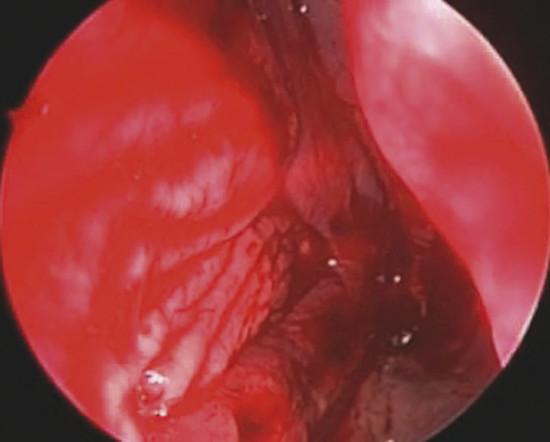

On the other side, in oval perforation with horizontal major diameter, a horizontal incision as long as the perforation major diameter is performed by a sickle knife on nasal mucosa 1 cm to the dorsal border of septal cartilage. The mucoperichondrial flap is then elevated from the perforation margin up to the incision. The flap is thus transposed downward and the borders of the perforation are sutured together with a 3–0 Vicryl suture (Fig. 19‑3).

In the case of rounded perforations, a rotation/advancement mucoperiosteal flap is designed by a rounded incision based posteriorly on the nasal-septal artery and elevated up to 1 cm from the choana (Fig. 19‑4). Also, in this case the flap is rotated to reach the inferior border of the perforation and sutured with a 3–0 Vicryl suture (Fig. 19‑5).